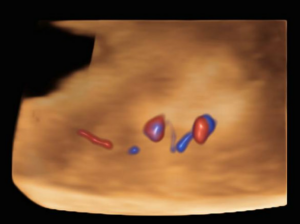

The ultrasound images demonstrated a single spinal column, two stomachs, and two hearts (Figure 2A). Two fused abdomens were observed, along with subcutaneous edema measuring 2.0 mm and 2.1 mm (Figure 2B). In addition, two pairs of moving legs were identified (Figure 2C). The trophoblast was located anteriorly, and a single corpus luteum was observed in the left ovary. Two follow-up examinations were required at 9 and 10 weeks of gestation to establish the diagnosis. At 9 weeks of gestation, the 3D ultrasound images lacked sufficient clarity for a definitive diagnosis (Figure 3). At 10 weeks of gestation, color Doppler imaging demonstrated two distinct cardiac activities, indicating the presence of two separate circulatory systems (Figure 4A). Three-dimensional imaging further revealed the face of one of the conjoined twins and confirmed the presence of two umbilical cords (Figure 4B).